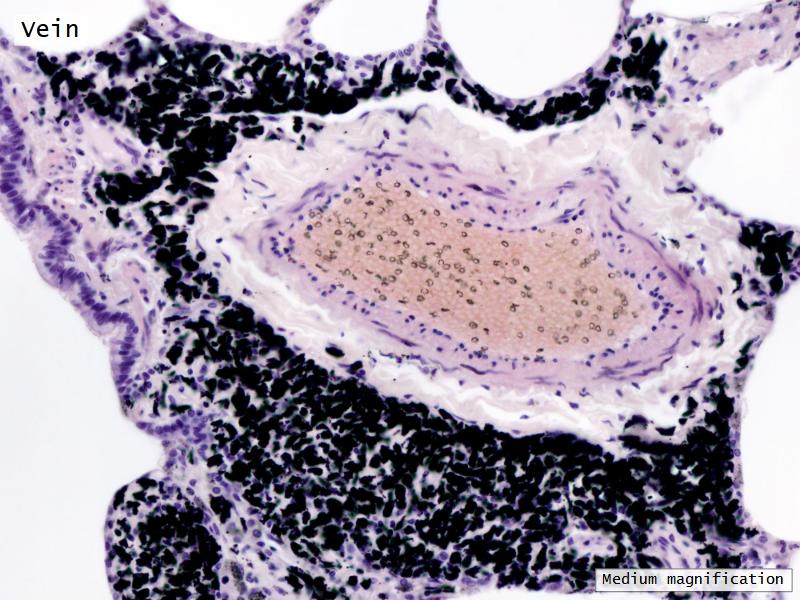

The cardiovascular system needs to be connected to the respiratory system.Path of O2 and CO2

Components of the Blood-Air Barrier?

What other barrier systems are found in the body?

What are the purpose of each of these barrier systems? Connected with physiology will unlock the pathology.

Barriers

- Blood-air

- Slide 72 & 74: Lung

Lungs